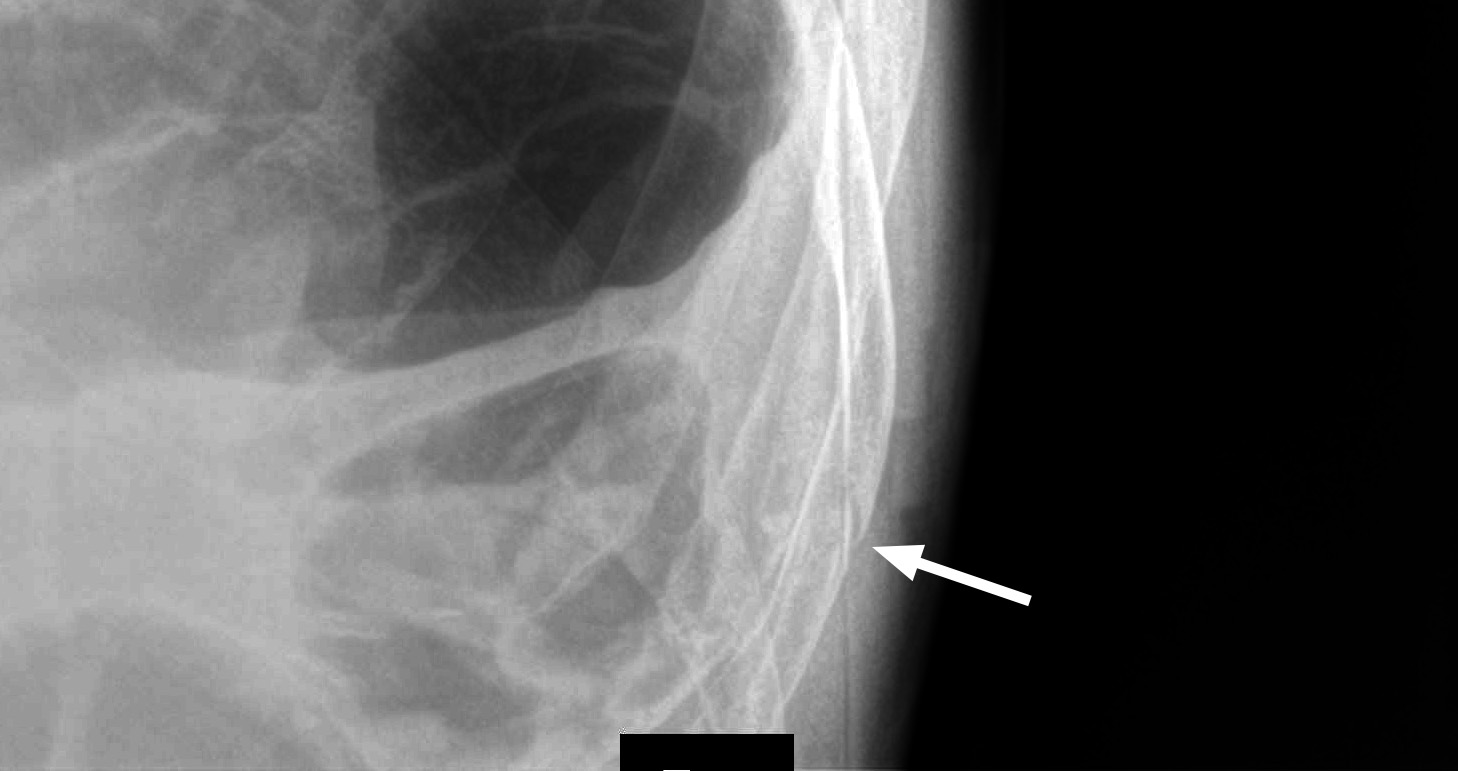

Мужчина средних лет, упал с лестницы 2 недели назад

Перелом ребра